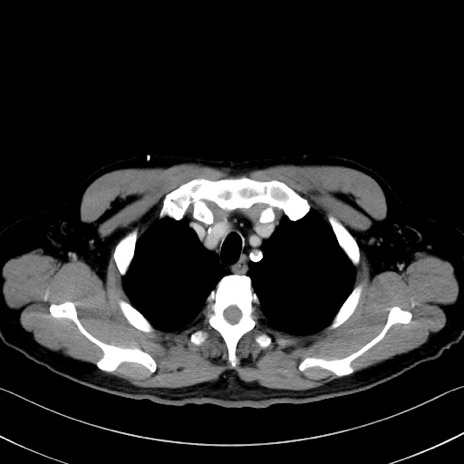

症例35(横断像)

【症例】70歳代 男性

【主訴】腹部膨満、嘔吐

【現病歴】昨日より腹部膨満感出現。本日増悪し、仙痛出現。嘔吐あり、受診。

【既往歴】糖尿病、胆摘後

【身体所見】BP 149/80mmHg、HR 74/min、BT 35.9℃、腹部:膨満、軟、圧痛なし。腸雑音減弱あり。上腹部正中切開瘢痕あり。

【データ】WBC 13500、CRP 1.72